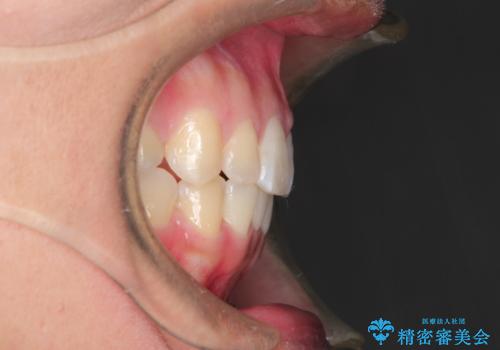

- 治療期間

- 2年6ヶ月

- 治療回数

- 10-30回

- 約90万円費用は治療当時の料金となります